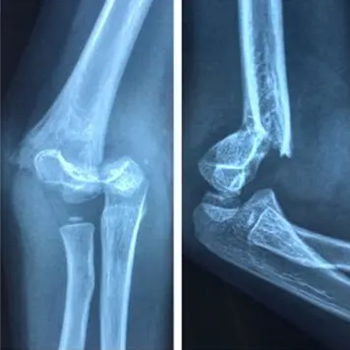

病例一:患儿女,7岁,摔伤

图 1 术前正侧位示肱骨髁上骨折